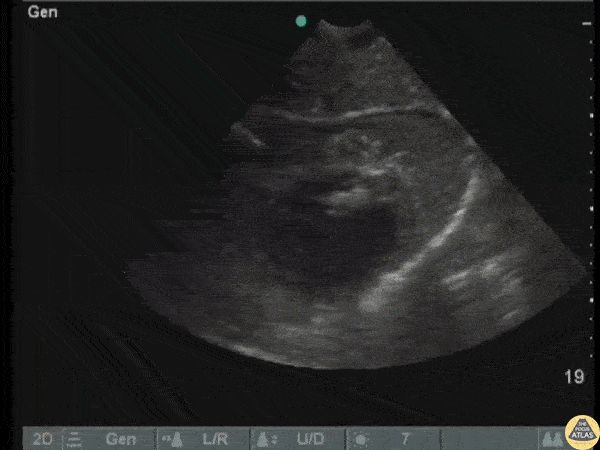

POCUS revealed a retained bullet near the left ventricular wall in a patient following a gunshot wound. Image courtesy of Robert Jones DO, FACEP @RJonesSonoEM Director, Emergency Ultrasound; MetroHealth Medical Center; Professor, Case Western Reserve Medical School, Cleveland, OH View his original post here